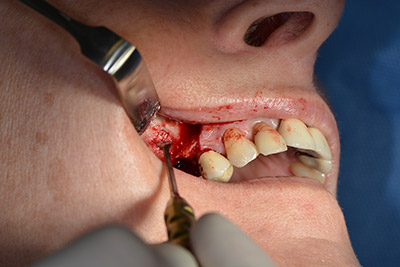

Die klassische Schnittführung (krestal, Entlastung bukkal) und das Präparieren des Mukoperiostlappens erlauben eine gute Übersicht.

In diesem Fall werden Sky Implantate (bredent) verwendet, deren chirurgisches Protokoll die Pilotbohrung mit etwa 1.200/min vorschreibt (Abb. 9).

Im nächsten Schritt wird die Sinusbodenelevation mit simultaner Implantation durchgeführt. Für die bukkale Fensterung der Kieferhöhlenwand gibt es auch hier bei der Implantmed an der ersten Position eine Voreinstellung.

Mit 35.000/min wird das Fenster angelegt und anschließend die Schneidersche Membran nach kranial präpariert. (Abb. 13 bis 14).

Präparieren der Schneiderschen Membran

Abb. 13

Schräge Bohrung

Abb. 14